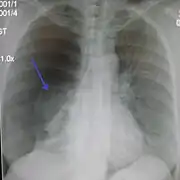

Chest X-ray

A plain chest radiograph, ideally with the X-ray beams being projected from the back (posteroanterior, or "PA"), and during maximal inspiration (holding one's breath), is the most appropriate first investigation.[30] It is not believed that routinely taking images during expiration would confer any benefit.[31] Still, they may be useful in the detection of a pneumothorax when clinical suspicion is high but yet an inspiratory radiograph appears normal.[32] Also, if the PA X-ray does not show a pneumothorax but there is a strong suspicion of one, lateral X-rays (with beams projecting from the side) may be performed, but this is not routine practice.[15][19]

It is not unusual for the mediastinum (the structure between the lungs that contains the heart, great blood vessels, and large airways) to be shifted away from the affected lung due to the pressure differences. This is not equivalent to a tension pneumothorax, which is determined mainly by the constellation of symptoms, hypoxia, and shock.[13]

The size of the pneumothorax (i.e. the volume of air in the pleural space) can be determined with a reasonable degree of accuracy by measuring the distance between the chest wall and the lung. This is relevant to treatment, as smaller pneumothoraces may be managed differently. An air rim of 2 cm means that the pneumothorax occupies about 50% of the hemithorax.[15] British professional guidelines have traditionally stated that the measurement should be performed at the level of the hilum (where blood vessels and airways enter the lung) with 2 cm as the cutoff,[15] while American guidelines state that the measurement should be done at the apex (top) of the lung with 3 cm differentiating between a "small" and a "large" pneumothorax.[33] The latter method may overestimate the size of a pneumothorax if it is located mainly at the apex, which is a common occurrence.[15] The various methods correlate poorly but are the best easily available ways of estimating pneumothorax size.[15][19] CT scanning (see below) can provide a more accurate determination of the size of the pneumothorax, but its routine use in this setting is not recommended.[33]

Not all pneumothoraces are uniform; some only form a pocket of air in a particular place in the chest.[15] Small amounts of fluid may be noted on the chest X-ray (hydropneumothorax); this may be blood (hemopneumothorax).[13] In some cases, the only significant abnormality may be the "deep sulcus sign", in which the normally small space between the chest wall and the diaphragm appears enlarged due to the abnormal presence of fluid.[16]